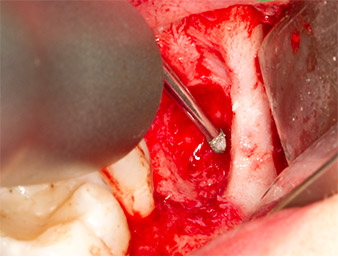

Tras una anestesia local y por conducción, el campo quirúrgico se abrió mediante los tejidos blandos para tener un acceso bucal-retromolar y se dejó expuesto (figura 3).

El tejido situado por encima del resto radicular no se había osificado por completo y constaba en su mayor parte de un tejido granulado con alteraciones inflamatorias (figura 4).